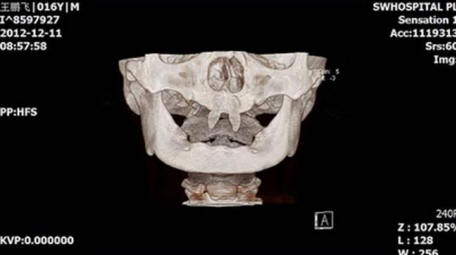

A kínai fiú két nagyon éles első fogat nőtt fel így vámpírnek tűnik. 2012 decemberében A Wang Hui nevű anya fiát, Wang Penfeit vitte a helyi emberhez kórház vizsgálatra. Chongqing Municipal Boy után a születés nagyon rosszul növekszik, és a szájában két élesnek látszott norvég menyhal.

Wang Hui megpróbálta megtudni ezeknek a fia megjelenésének okát rendellenes képződmények, és számtalan látogatott orvosok, de ez nem hozott sok sikert. Orvosok A Délnyugati Kórház szerint fia megtehető műtét csak akkor, ha felnőtté válik.

fénykép nyílt forrásokból

Ennek a műveletnek a költségei 70 000 és 80 000 között változhatnak RMB, körülbelül 15 000 dollár. Wang Hui szerint fia egyre inkább válik egyre inkább visszavonulnak, és gyakran harcolnak osztálytársakkal, akik suttognak róla, vagy figyelmesen néznek rá.